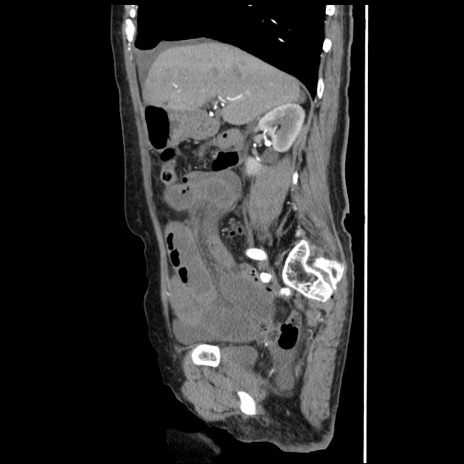

横断像

【症例】80歳代女性

【主訴】腹痛

【現病歴】8時間前から腹痛あり来院。

【既往歴】糖尿病、脂質異常症、子宮体癌にて子宮全摘術

【身体所見】意識清明・会話良好だが腹痛で苦悶様、全腹部にわたって反跳痛と圧痛あり

【データ】WBC 13600、CRP 0.14、LDH 224、CK 90